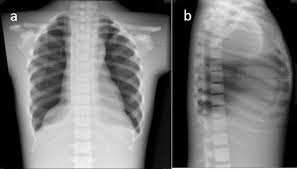

How many x rays are dangerous? What matters is the intensity of the radiation. The lowest radiation exposure to cause radiation sickness is about 100 rem (1 sv). They are advised only at certain ages. Those who don't have cavities can go a year or two between. The exposure we are concerned about is lifetime exposure, not annual exposure. In the case of standard procedures, there is no or negligible chance of risk. How are x rays harmful to the earth?

This level of exposure will also increase your risk of a fatal cancer over the next few to several decades by about 5%.

(the atmosphere acts to absorb or deflect some of the cosmic radiation. The lowest radiation exposure to cause radiation sickness is about 100 rem (1 sv). More images for how many x rays are safe in a year » This level of exposure will also increase your risk of a fatal cancer over the next few to several decades by about 5%. What matters is the intensity of the radiation. How are x rays harmful to the earth? What are the hazards of x rays? You have to understand that the frequency of the radiation doesn't matter. How many x rays are dangerous? The dosage is less and the image quality has improved. The exposure we are concerned about is lifetime exposure, not annual exposure. Those who don't have cavities can go a year or two between. Why are x rays dangerous?